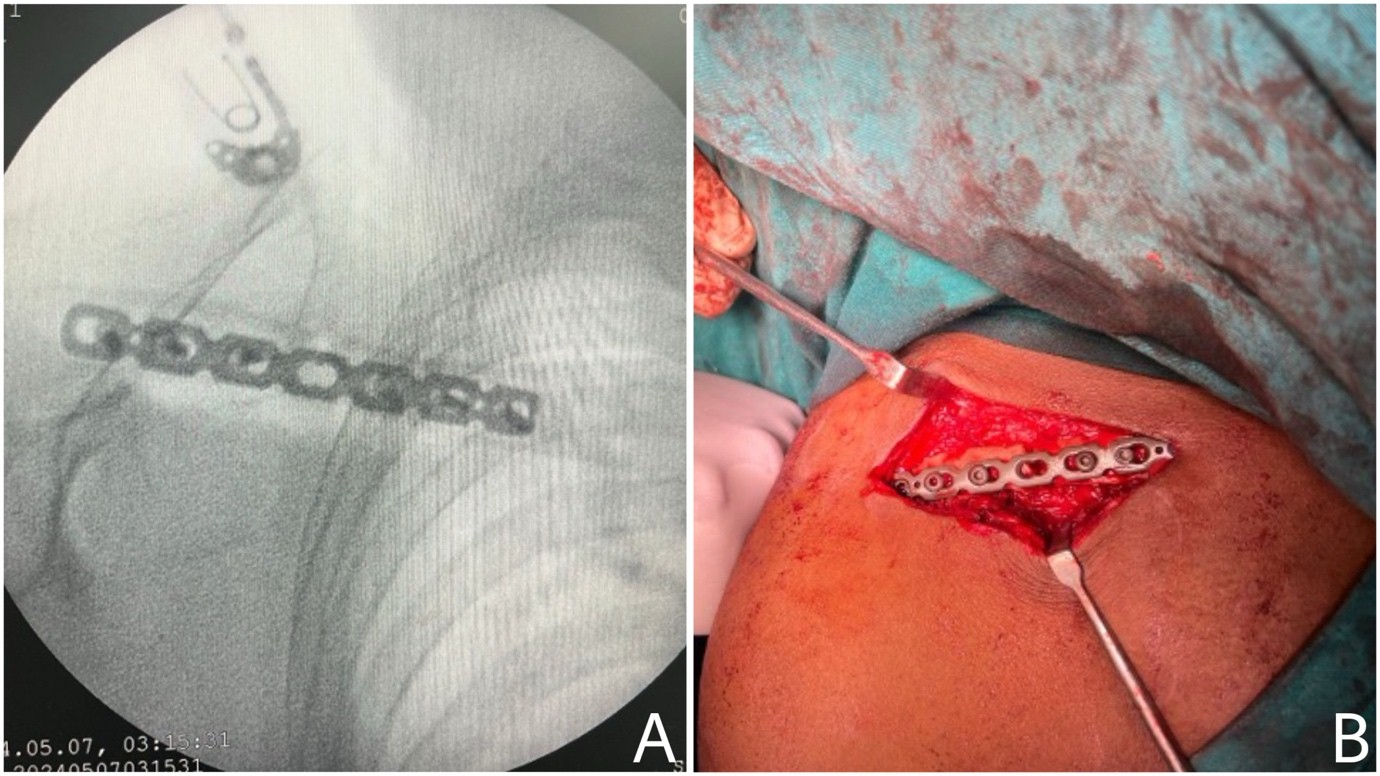

About 42 participants were recruited in this research work, with most (54.8%) falling within the 18–40-year age group, followed by 28.6% between 41 and 60 years, and 16.7% aged 60 years or older. Males comprised 69% of the study population, while females accounted for 31%. Fractures were slightly more common on the right clavicle (52.4%) than the left (47.6%). Most participants (76.2%) had displaced middle-third clavicle fractures, followed by comminuted displaced fractures (23.8%). The most frequently observed AO clavicle grading was 2B1, seen in 24 cases (57.1%). Fig. 2 shows the Intraoperative images with key surgical steps, including incision marking (Fig. 2a), fracture reduction (Fig. 2b), plate fixation (Fig. 2c), and confirmation of implant positioning using intraoperative C-arm imaging (Fig. 2d).

Figure 2: Intraoperative images illustrating the surgical procedure. *(a) Intraoperative C-arm imaging confirming proper implant positioning (b) Plate fixation following reduction.